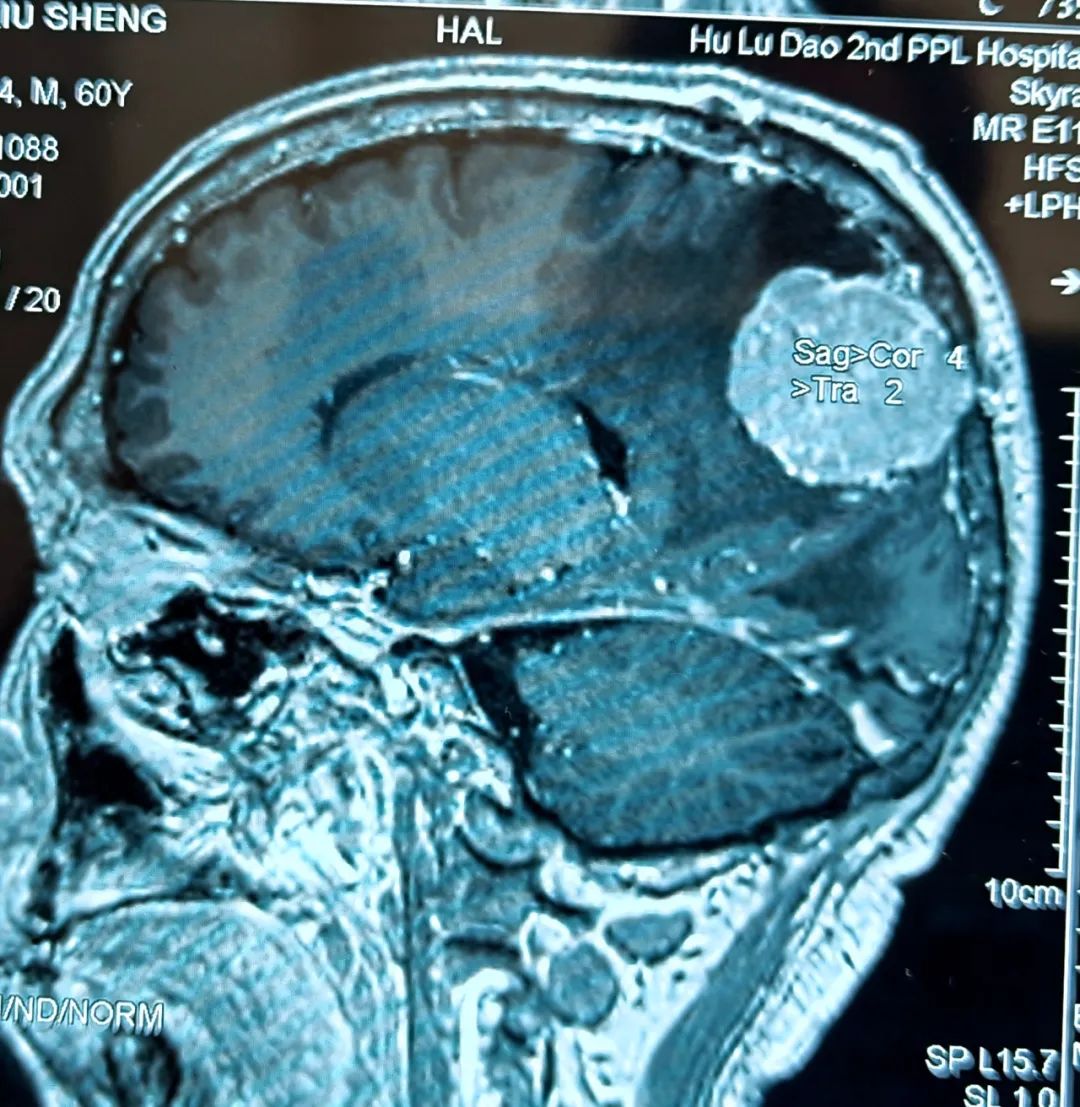

經(jīng)過團(tuán)隊成員的共同努力,手術(shù)順利完成,患者安返病房。術(shù)后在神經(jīng)外科護(hù)理團(tuán)隊的精心護(hù)理下,患者病情恢復(fù)良好,言語及四肢功能無任何障礙,術(shù)后一周便可行走自如。

- 患者術(shù)后核磁 -